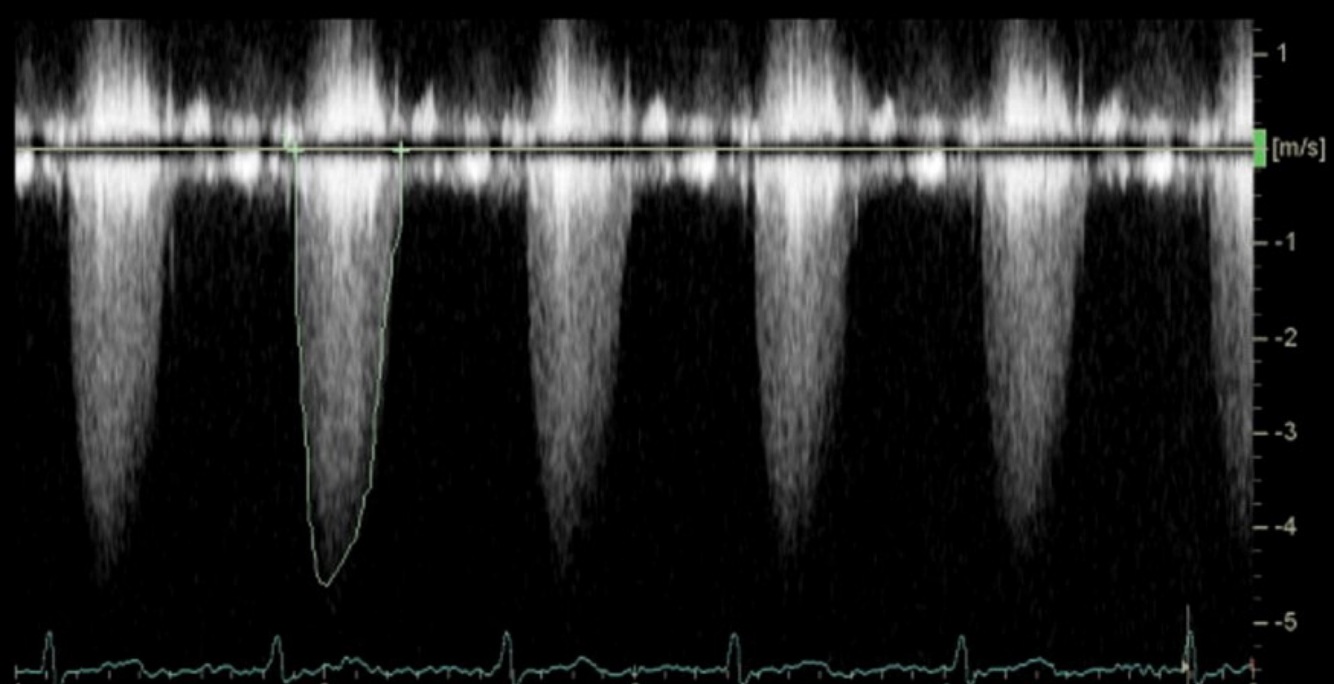

Which window has this pedoff CW waveform been taken from?

Apical

(This is severe stenosis, because it is over 4cm/s)